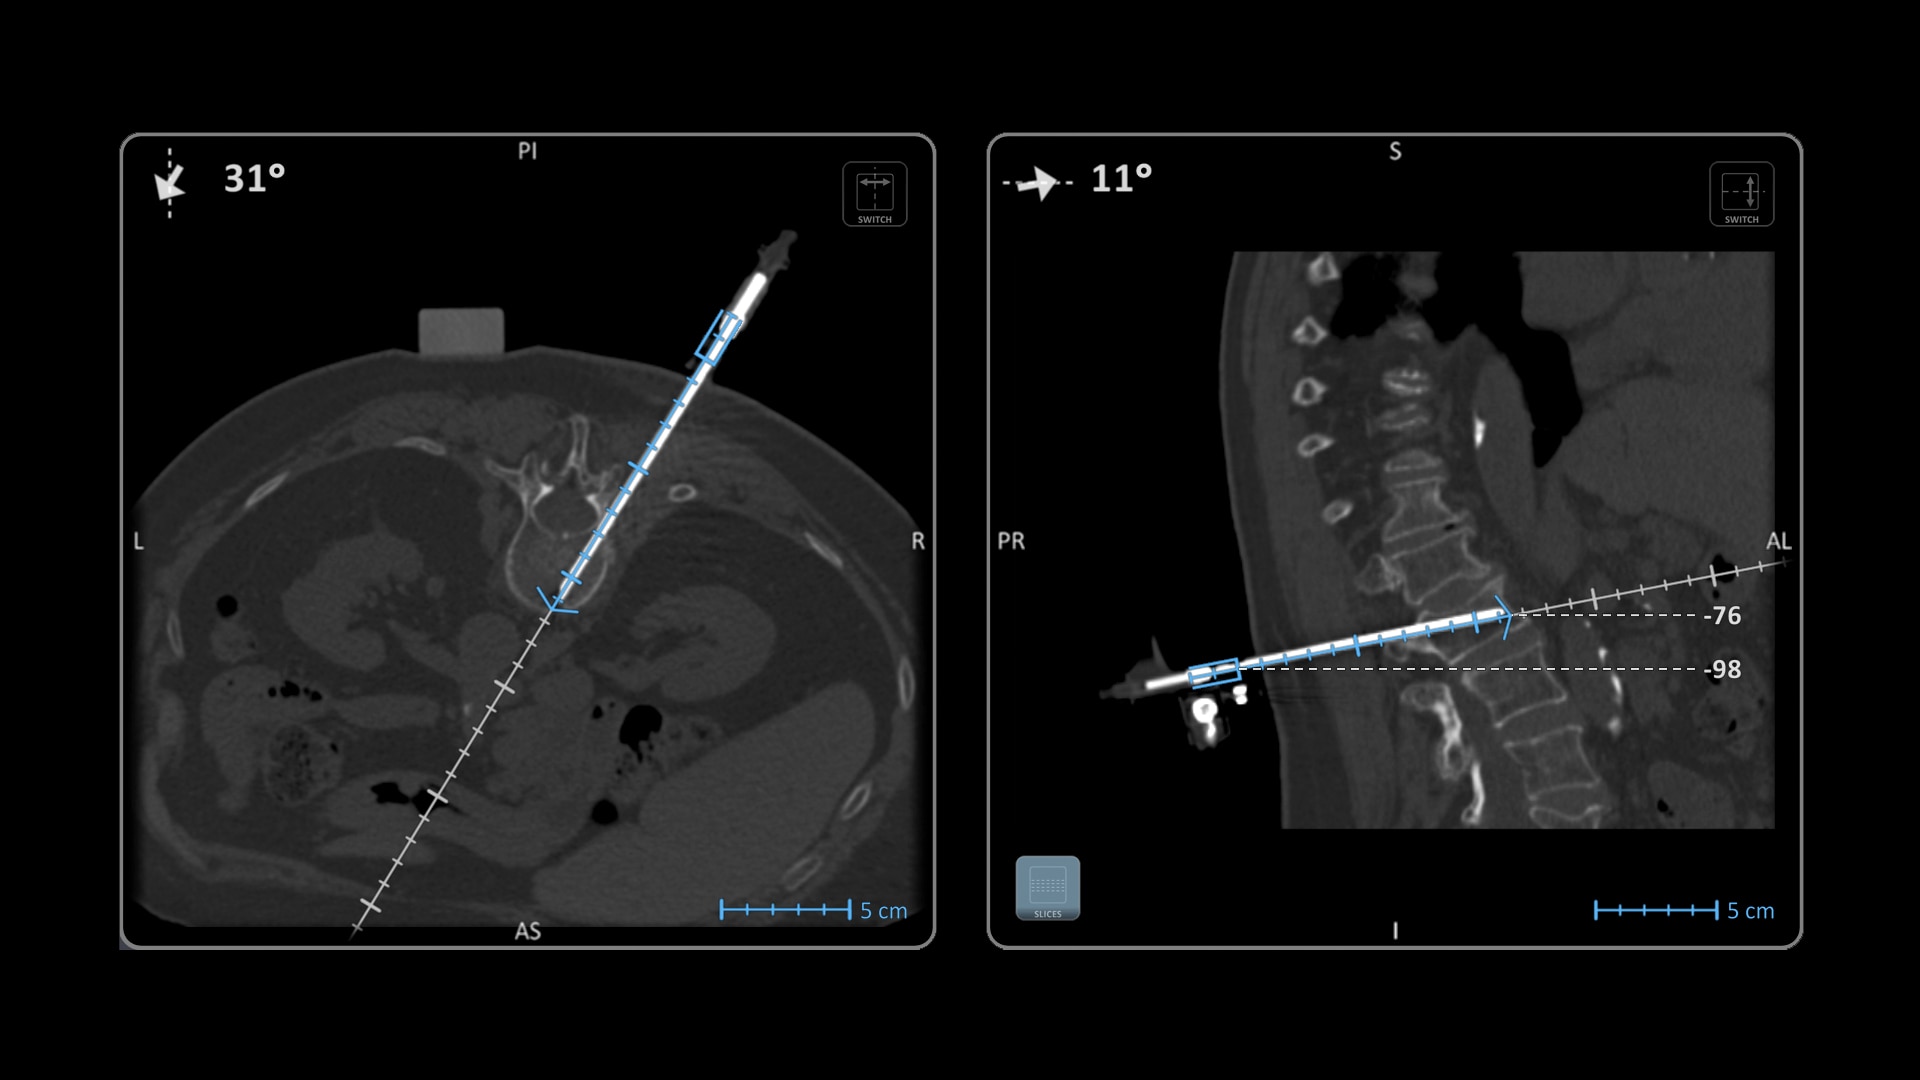

Versatility

Ideal to use with various percutaneous interventions² with various complexity